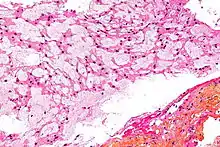

There are three histological variants of chordoma: classical (or "conventional"),[13] chondroid and dedifferentiated.

- The histological appearance of classical chordoma is of a lobulated tumor composed of groups of cells separated by fibrous septa. The cells have small round nuclei and abundant vacuolated cytoplasm, sometimes described as physaliferous (having bubbles or vacuoles).

- Chondroid chordomas histologically show features of both chordoma and chondrosarcoma.